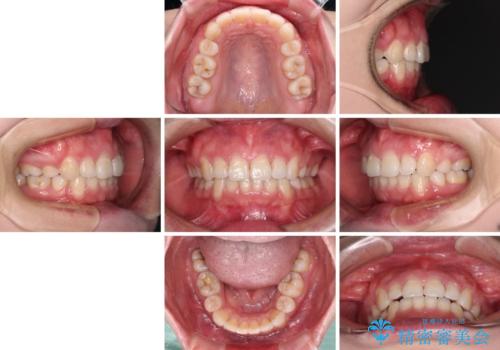

- 治療期間

- 2年6ヶ月

元々上下正中の位置はずれていましたが、治療中によりズレが大きくなったので、元の位置に戻すため治療期間を余計に要しました。

横顔の印象が大きく改善され、患者様には大変満足していただきました。